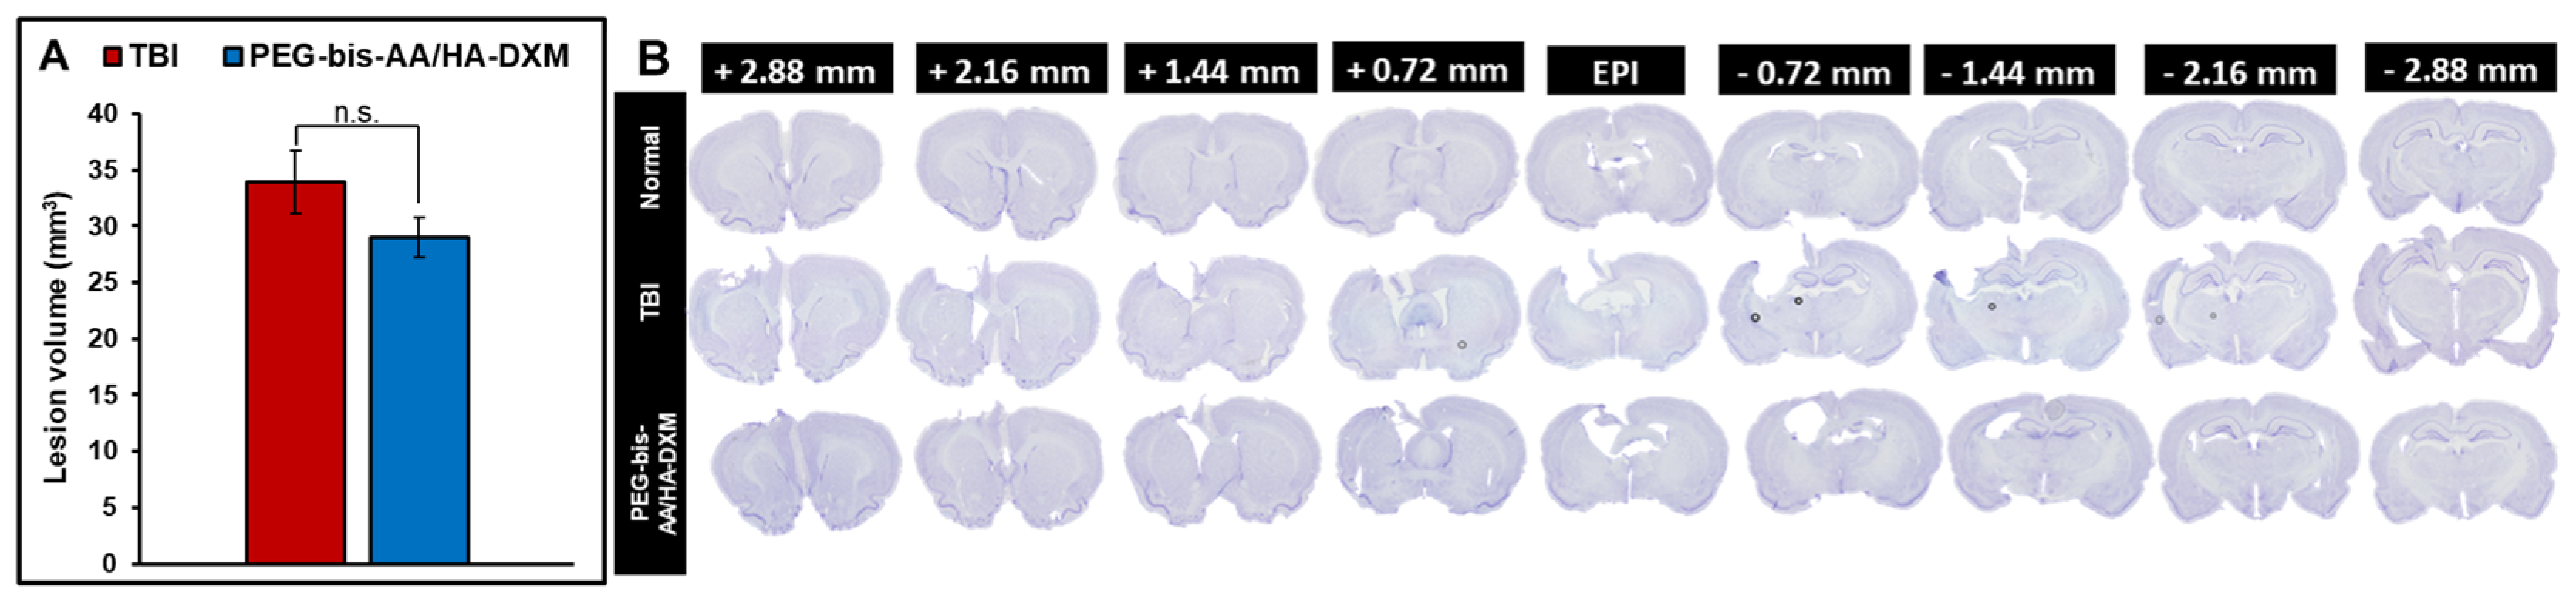

2.2. PEG-Bis-AA/HA-DXM Reduces Lesion Volume